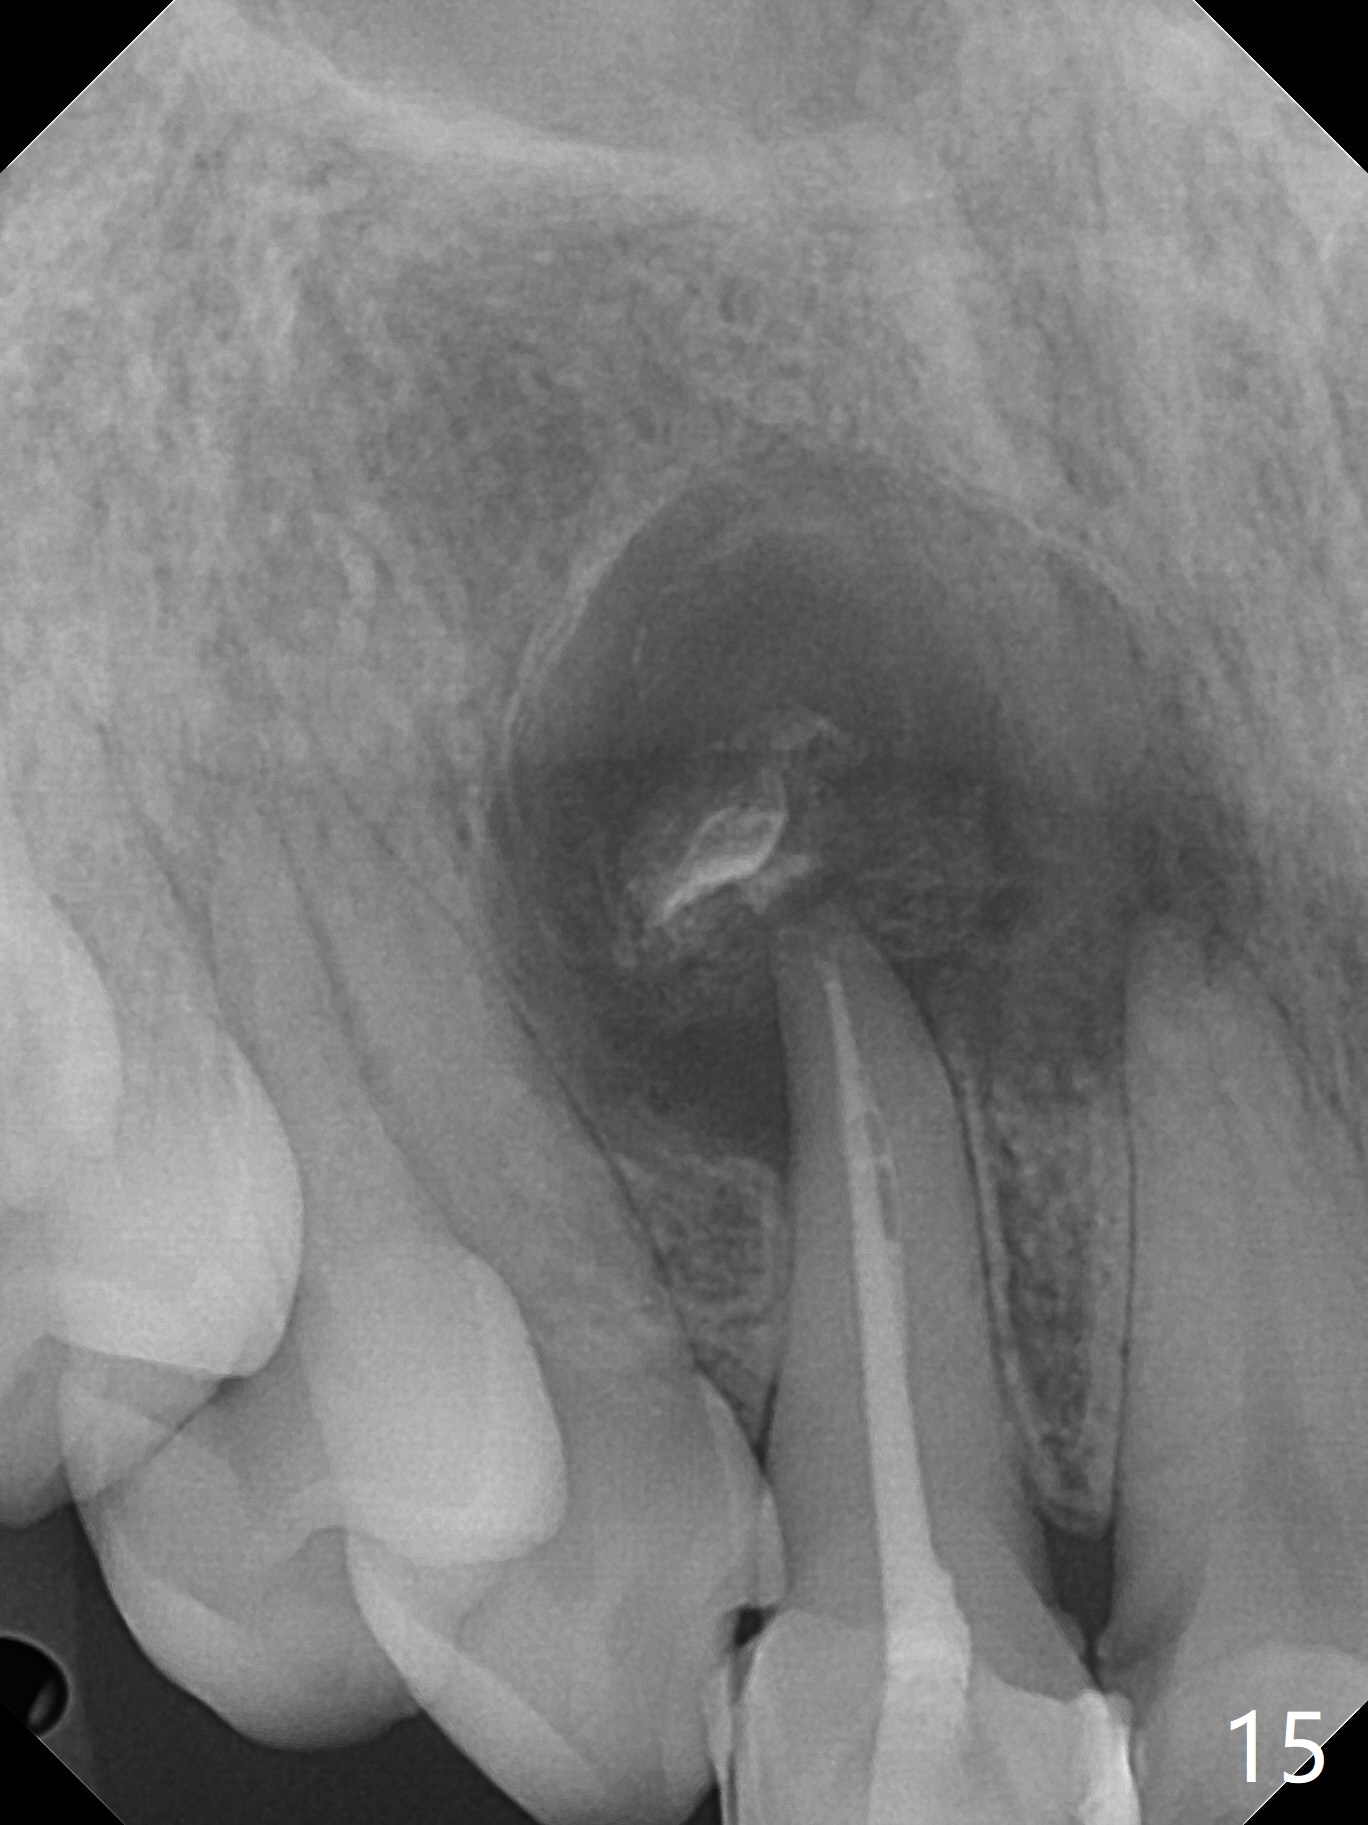

A 47-year-old woman (dental phobic) presented to clinic 9.5 years ago with periapical radiolucency (PARL) at #7 and 9 (Fig.1). RCT was done at #9 because of fistula and symptom 6 months later (Fig.2). While PARL increases at #7 without symptom, that at #9 disappears 8.5 years postop. Three months later, the patient returns for #7 RCT because of the abscesses (Fig.4 *) and pain. Intraop PA is taken with a 30/.06 rotary file in the canal with 19 mm working length (Fig.5). After use of #15 hand file for 20 mm, Ca(OH)2 paste is applied in the canal. When the rubber dam is removed, the abscesses enlarge (Fig.6), which may be related to sodium hypochlorite leakage. A dental explorer is used to try to find a bony opening to the large PARL without success (Fig.7). A postop PA reveals the leakage of Ca(OH)2 paste (Fig.8). Review of the preop PA (Fig.3,9) and intraop PAs (Fig.5,10) shows possible apical resorption and open apical foramen, which is the basis for the paste leakage (Fig.8,11). Careful analysis (with magnification and room light off) of pre- and intra-op PAs should be able to avoid use of #15 hand file out of apical constriction and the complication. The abscess has receded 1 month later (Fig.12). The paste has been resorbed 1 month later (Fig.13). A 30/.06 Gutta Percha is inserted at 18.5 mm (Fig.14 vs. 30/.06 file at 19 mm, 15 file at 20 mm last visit). Fig.15 is the final PA after closure of the access with composite (Fig.15).